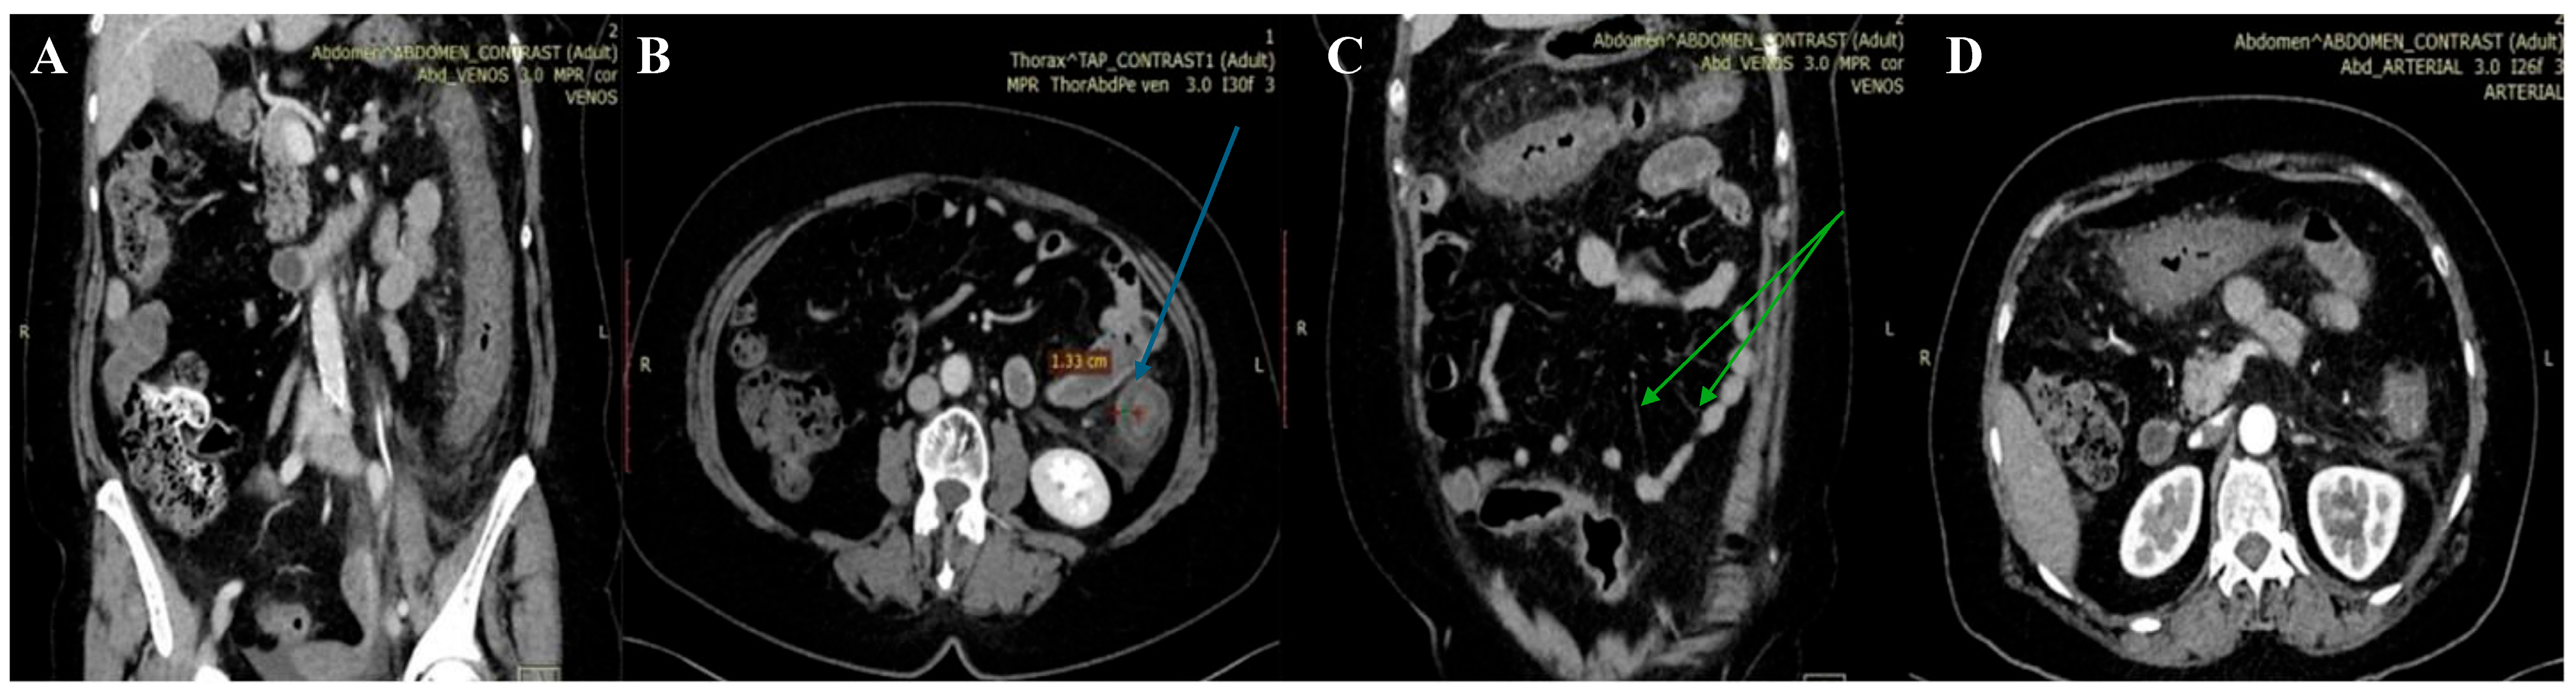

Microbiological investigations ruled out Clostridium difficile, Shigella, Salmonella, and parasitic involvement, and a PCR-based multiplex pathogen GI test detected Shiga-like toxin-producing Escherichia coli (STEC) stx1/stx2 genes. The STEC serotype and subtype could not be determined. The abdominal CT revealed a spastic transverse and descendent large intestine with a thickened circumferential mucosa, suggestive of an inflammatory and infectious process, which progressed over the following days (Figure 1 and Figure 2).

On the third day, the patient underwent a second abdominal CT scan, which showed extensive colonic lesions up to the hepatic flexure and down to the sigmoid and rectum (Figure 2), preserving the mesenteric artery with contrast medium. This picture was compatible with the micro-ischemic lesions found in infectious ischemic colitis [6,7].

Tomographic features very suggestive of bacterial colitis are (1) continuous distribution, (2) an empty colon, (3) the absence of fat stranding, (4) the absence of a “comb” sign, and (5) the absence of enlarged lymph nodes [2]. According to these criteria, our patient had extensive and continuous distribution, collapsed intestines, and the absence of enlarged lymph nodes. However, contrarily, she had pericolic fat stranding and an incomplete “comb” sign, which made the final diagnosis more difficult to determine.

Figure 2. Second abdominal CT. Extensive and continuous lesions, up to hepatic flexure and down to sigmoid with pericolic fat stranding. Coronal (A,C) and axial planes (B,D) respectively.